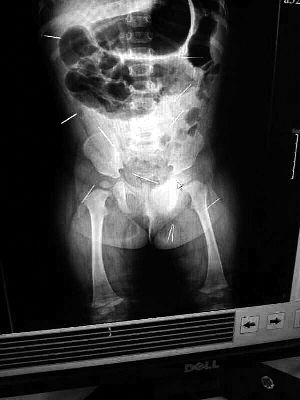

山東聊城11個(gè)月女?huà)胼孑妫ɑ┮伤票蝗艘?2根鋼針插滿臀部、腹腔等部位,昨天在兒童醫(yī)院會(huì)診后,醫(yī)生稱(chēng)3根針靠近胸腔最危險(xiǎn),首批先行取出,預(yù)計(jì)將在下周二手術(shù)。孩子父母稱(chēng)孩子一直由家人照顧,自家與他人并無(wú)冤怨。山東警方表示正在偵破中,不便透露案情。

“要不是當(dāng)初那幾個(gè)紅點(diǎn),可能到現(xiàn)在我們還不知道孩子身體里有鋼針!”昨天,在兒童醫(yī)院住院處,萱萱爸爸范先生稱(chēng),日前原本很愛(ài)笑的萱萱突然變得有些焦躁,一抱起來(lái)就哭,孩子母親偶然間在萱萱屁股上發(fā)現(xiàn)了幾個(gè)小紅點(diǎn)兒,原以為是蚊蟲(chóng)叮咬,就醫(yī)結(jié)果卻讓人不寒而栗?!搬t(yī)院拍出的片子上,萱萱的體內(nèi)有12根鋼針,插滿臀部、腹腔、骨盆等各個(gè)部位?!狈断壬榻B,因?yàn)殇撫樢焉钊塍w內(nèi),要是孩子不哭鬧,他們很難發(fā)現(xiàn)。

北京晨報(bào)記者了解到,目前體內(nèi)的12根鋼針多分布在孩子的臀部,一根在腹部,其余3根在胸腔附近,其中一根很接近心臟。“因?yàn)楹⒆犹?,醫(yī)生們害怕取針的時(shí)候?qū)λ斐蓚?,在胸腔附近?針可能會(huì)威脅她的生命”。